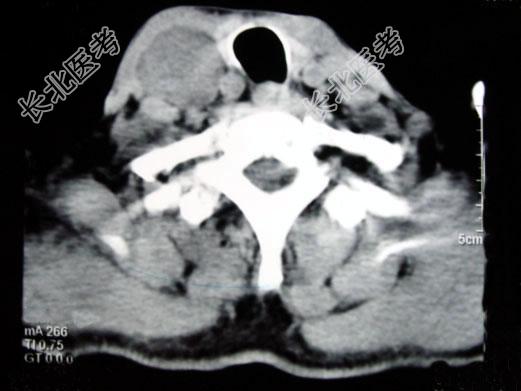

- 多项选择题男,70岁, 右侧颈部无痛性肿块3个月,CT扫描如图所示, 正确的描述或诊断是 ( )

A、右侧颈动脉间隙内见类圆形软组织肿块影,密度欠均匀,边缘光整

B、右侧颈静脉被推压至肿块外后方

C、右侧颈动脉被推压至肿块内后方

D、迷走神经源性肿瘤

E、交感神经源性肿瘤